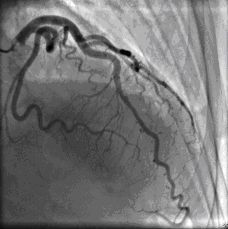

Cardiac catherization on hospital day 15 revealed normal coronary arteries (Figure 1) with anterobasal and posterobasal hyperkinesis, anterolateral and diaphragmatic hypokinesis, and distal ballooning on ventriculography. Ventriculography revealed global LV depression with EF of 45% (Figures 2, 3).

Fig1

Figure 1-Cardiac catherization on hospital day 15 revealed normal coronary arteries.